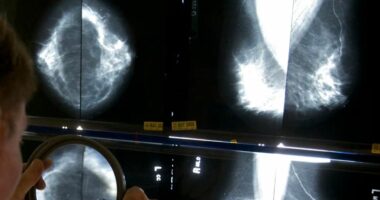

Nisma u prezantua nga ministrja e Shëndetësisë Albana Koçiu për të lehtësuar aksesin ndaj këtij shërbim shëndetësor.Në muajin e ndërgjegjësimit për kancerin e gjirit u kryen gjysma e mamografive të gjithë vitit. Më shumë se 12 mijë nga rreth 25 mijë në total.

Ndërsa tetori rozë u mbyll mjekët vijojnë me thirrjen për të kryer një eko apo mamografi pasi kapja e hershme e sëmundjes shpëton jetë.